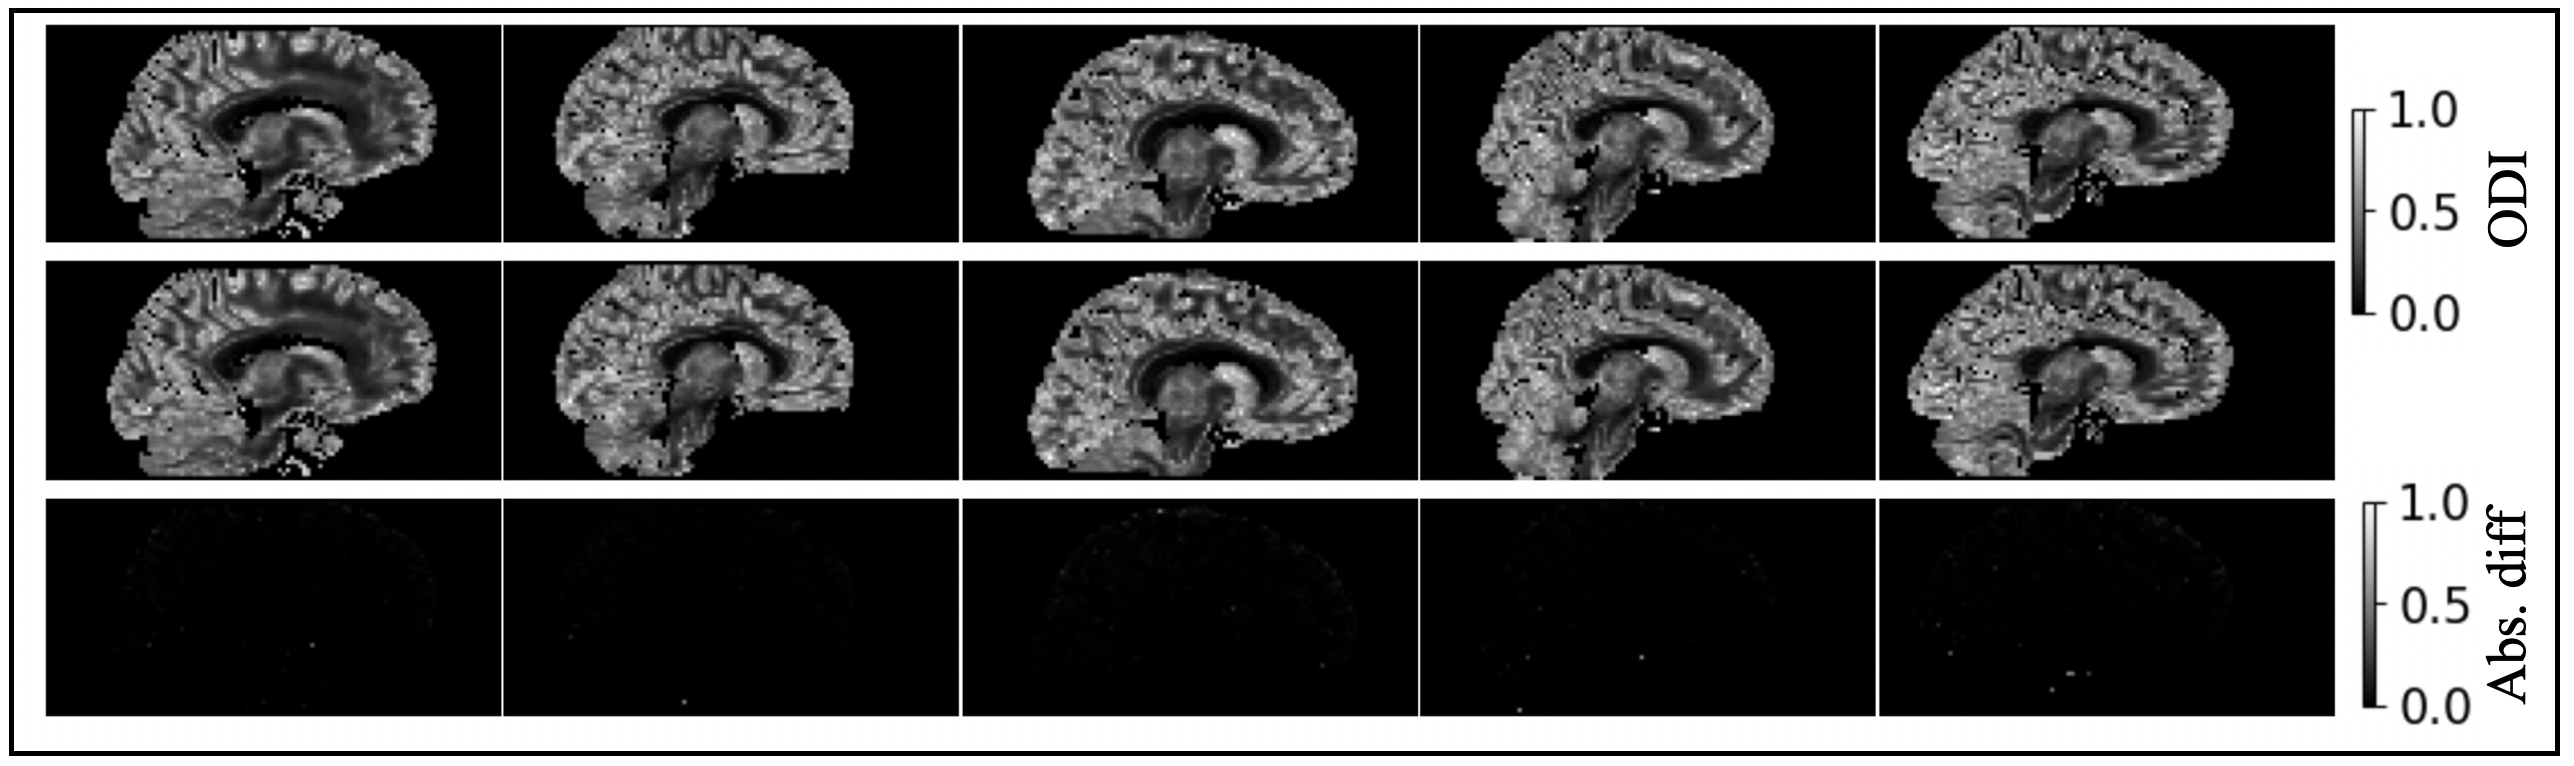

We show the absolute difference between the voxel-wise Bammer correction and the proposed approximation for iVF (Figure 3), cVF (Figure 4), and ODI (Figure 5) for five subjects. The mean absolute difference in all three NODDI scalar metrics are less than 10-2 between the techniques. The Cohen’s d between the voxel-wise correction and proposed approximation was <0.2 for all subjects. This suggests the approximation does not change the DW-MRI information substantively from the standard Bammer correction technique.

Validation of proposed approximation in orientation dispersion index (ODI). Each column represents one subject. The ODI after voxel-wise gradient nonlinearity correction are shown in the first row of each panel. The ODI after the proposed approximation are shown in the second row. The absolute difference between the two are shown in the third row of each panel. The absolute difference of the scalar maps are near zero.